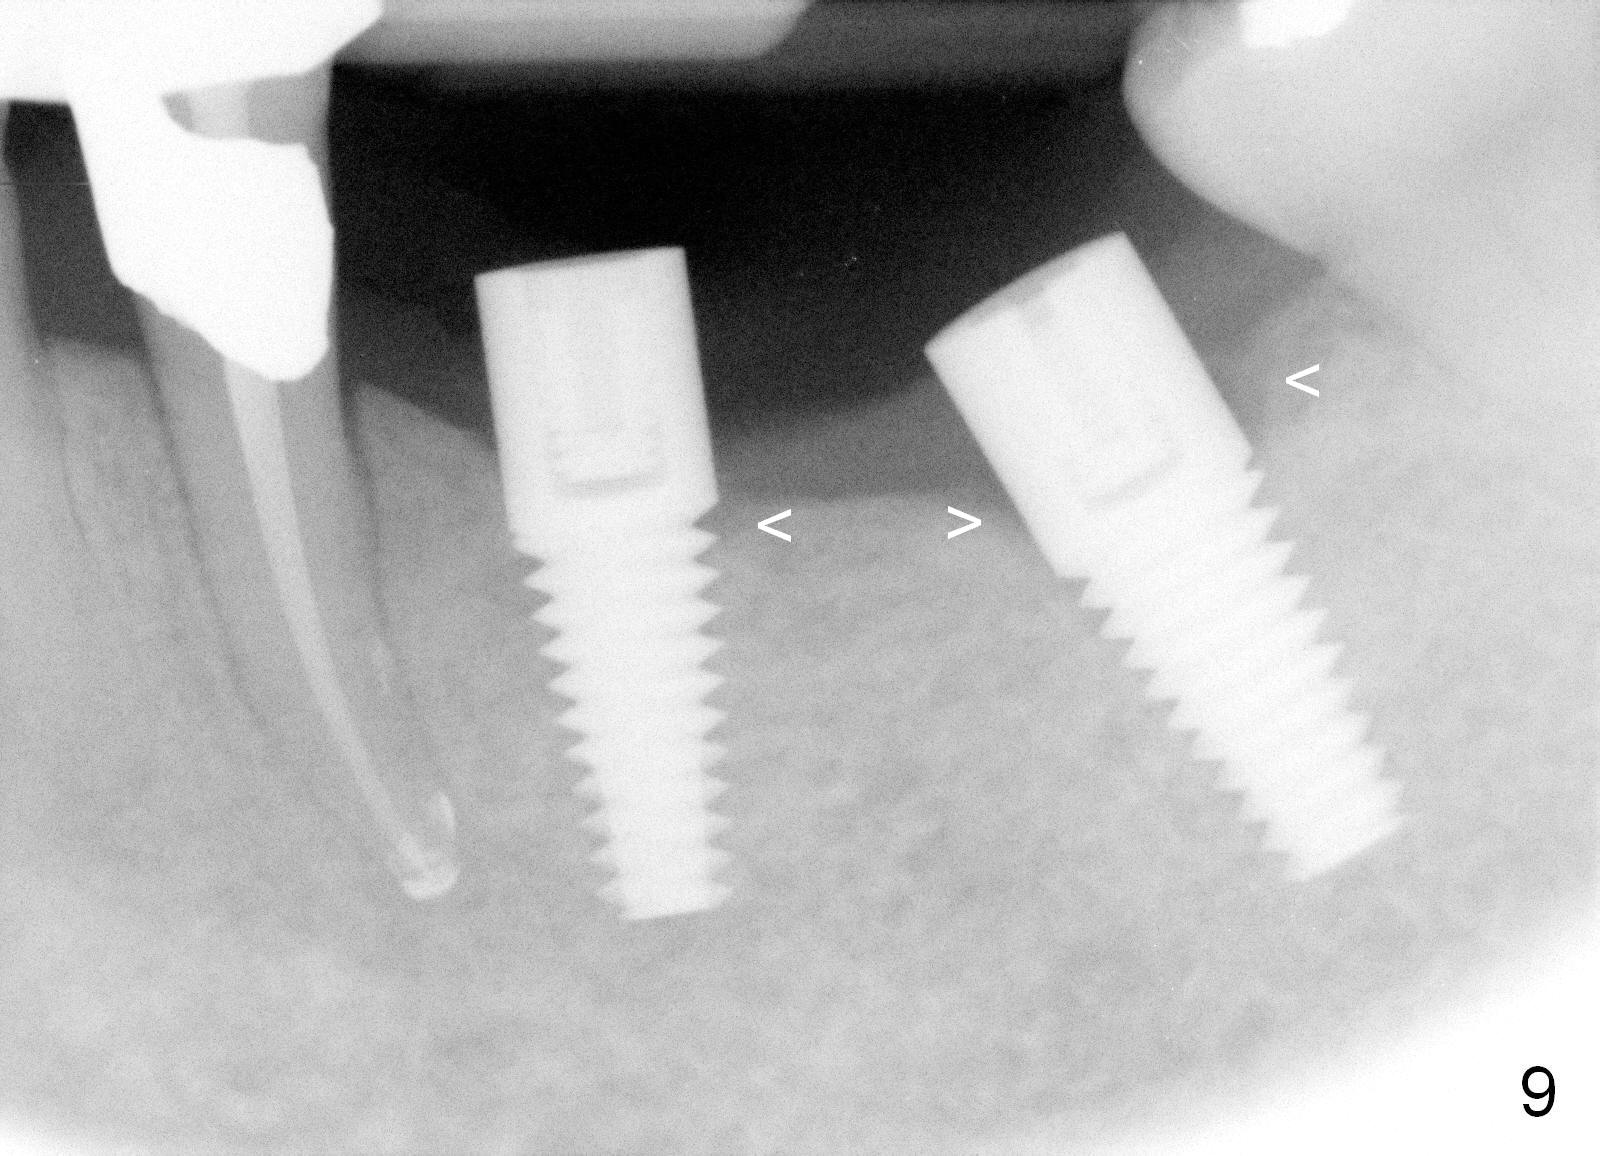

One year 2 months post root canal therapy at #20 (Fig.4), osteotomies are initiated at #18 and 19.  The trajectory at #19 is subsequently corrected (Fig.5); that of #18 should be also corrected (arrow).  The fact of the narrow ridge (Fig.6) is also ignored intraop.  Without further adjustment, the osteotomies are enlarged (Fig.7) and the implants are placed (Fig.8: 4.5x14, 5x14 mm).  As expected, the buccal coronal implant surface is exposed.  The buccal plate is decorticated with placement of autogenous bone graft.  Periodontal dressing is applied.  Postop, the wound is infected with wound gapping.  With irrigation, the wound finally heals.

Three months postop, crestal bone has started to resorb (Fig.9 arrowheads).  Resorption gets worse over time (Fig.10: 4 months post cementation, 11 months postop) (Fig.11: 1 year 2 month post cementation).  On the other side (#30), postop bone resorption is not so severe.  The patient's main concern is that she does not have normal taste ever since she got the implants.